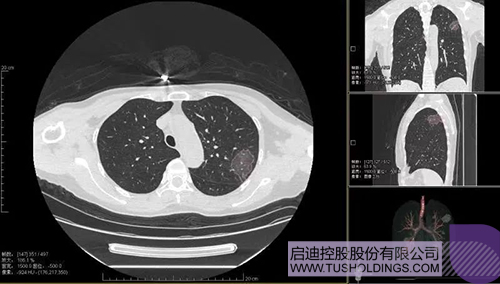

2020年2月11日,啟迪科服投資企業(yè)—神州德信推出新冠肺炎檢測及量化智能分析系統(tǒng),積極助力一線醫(yī)務(wù)人員科學精準防疫。